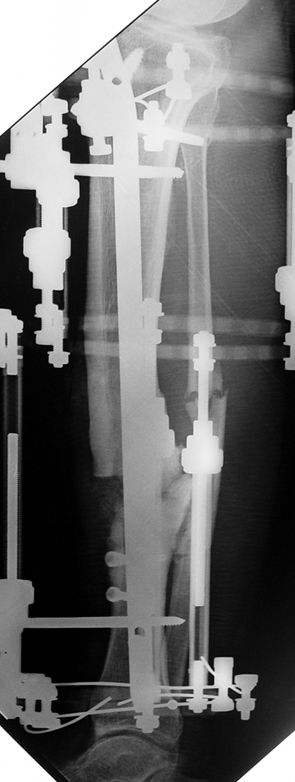

Vaka 3